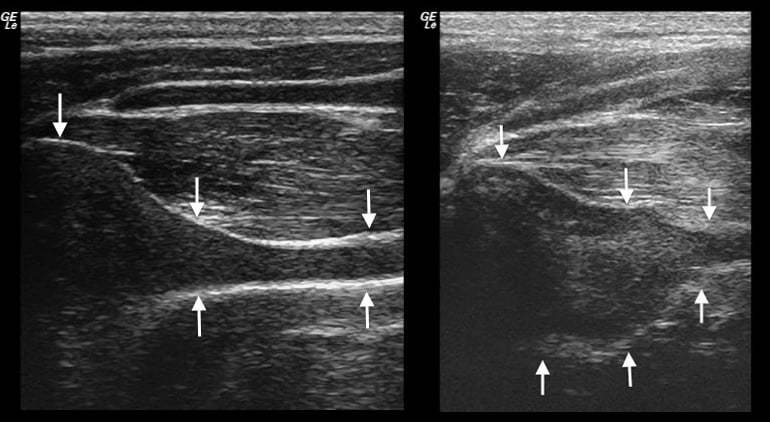

Ultrasonography could be a valuable adjunct tool for diagnosing equine arytenoid chondritis.

Ultrasonography could be a valuable adjunct tool for diagnosing equine arytenoid chondritis.